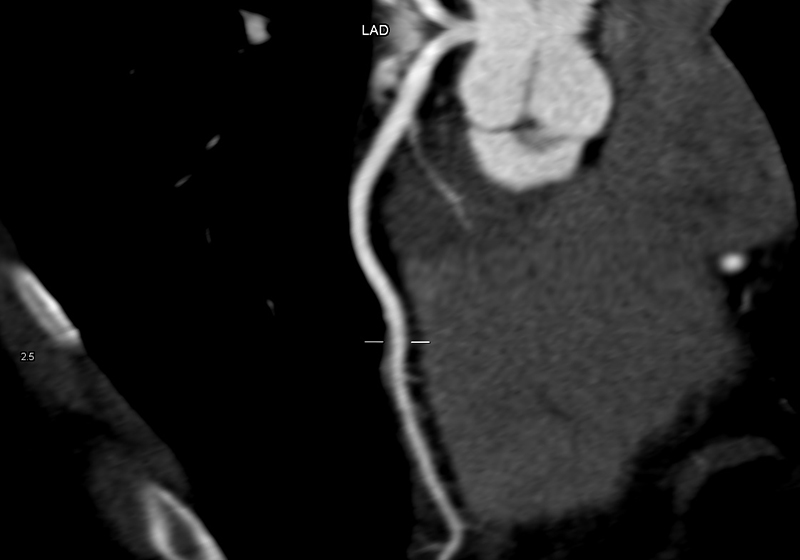

Über eine 3D-Nachverarbeitung werden die Herzkranzgefäße sowie eventuelle Engstellen und Verkalkungen dargestellt und vermessen. Sofern vorhanden, können an dieser Stelle auch Stents oder Bypässe auf deren Durchgängigkeit überprüft werden.